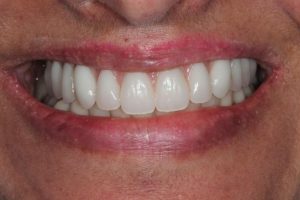

Upper Front Tooth Implant

This patient had broken their upper front tooth and the exisitng dental crown had fallen off. The underlying root was unfortunatley irreparable.

The dental root was subsequently removed and an implant placed at the same time. The implant had a temporary crown placedon the same day.

The ‘After’ photos shows the final crown that was made after 3 months. The implant crown was made to match the form and colour of the exisiting teeth to give an overall natural aesthetic finish.